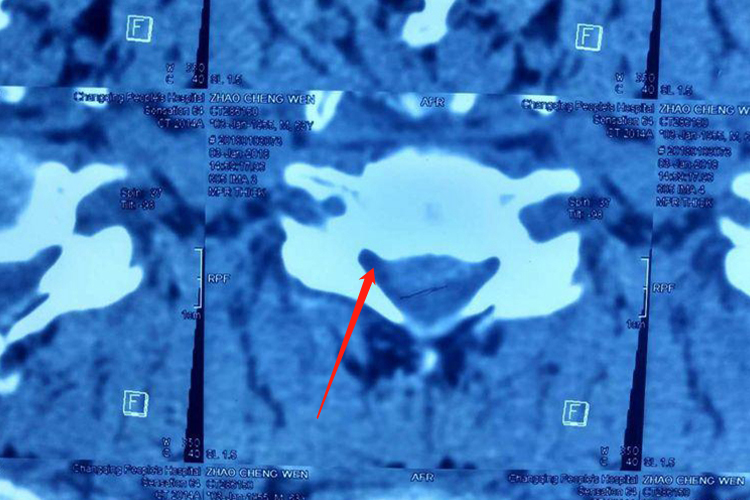

脊髓型颈椎病:患者先从下肢双侧或者单侧发沉、发麻开始,随之出现行走困难,下肢肌肉发紧,抬步慢,不能快步走,重者步态蹒跚。最明显的体征是四肢肌张力升高,下肢往往较上肢明显。CT平扫可见颈椎间盘突出,椎管明显受压。核磁共振检查可显示颈椎脊髓受压。